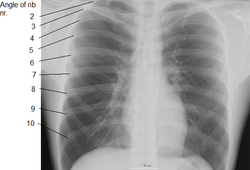

Čovjek, bez obzira na spol, ima 12 pari rebara (odnosno 24 rebra). Prvih je sedam hrskavično povezano s prsnom kosti (lat. sternum). Naredna tri para, poznata kao "lažna rebra", dijele hrskavičnu vezu sa prsnom kosti (vidi slike). Zadnja se dva para nazivaju tekuća ili kralježna rebra (lat. costae fluitantes) jer su vezana samo za kralježnicu, a ne za sternum ili hrskavicu sternuma. Nekim ljudima nedostaje jedan od zadnja dva para rebara, dok neki imaju i treći par. Uklanjanje rebara je kirurški zahvat odvajanja rebara iz terapeutskih ili kozmetičkih razloga.

Galerija slika niže prikazuje ljudska rebra: